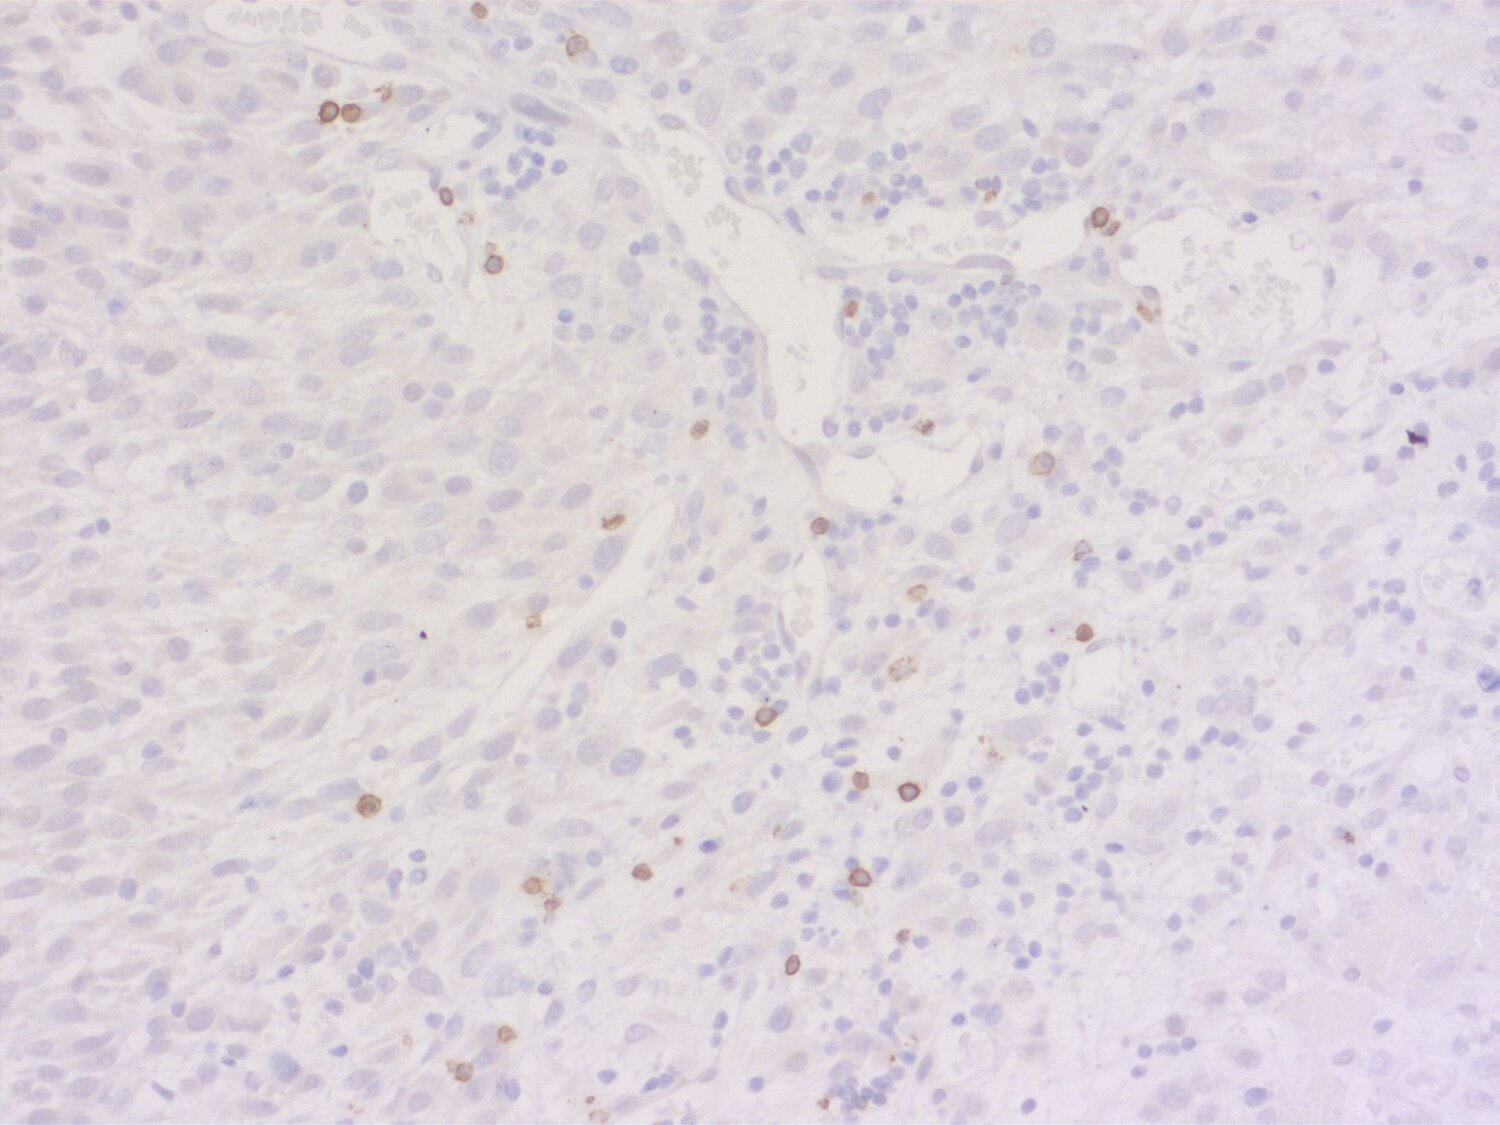

Indirect immunostaining of a formalin fixed paraffin-embedded mouse breast cancer model with rabbit anti-mouse CD19 (cat. no.: HS-439 003; DAB). Nuclei have been visualized by haematoxylin staining (blue).

IHC: 1 : 500 gallery

IHC-P: 1 : 100 gallery

Immunohistochemistry (IHC) on 4% PFA perfusion fixed tissue with 24h PFA post fixation. Immunoreactivity is usually revealed by fluorescence or a chromogenic substrate. Some antibodies require special fixation methods or antigen retrieval steps. For details, please refer to the ”Remarks” section.

Immunohistochemistry (IHC-P) of formalin fixed, paraffin embedded (FFPE) tissue (some antibodies require special antigen retrieval steps, please refer to the ”Remarks” section). Immunoreactivity is usually revealed by fluorescence or a chromogenic substrate.